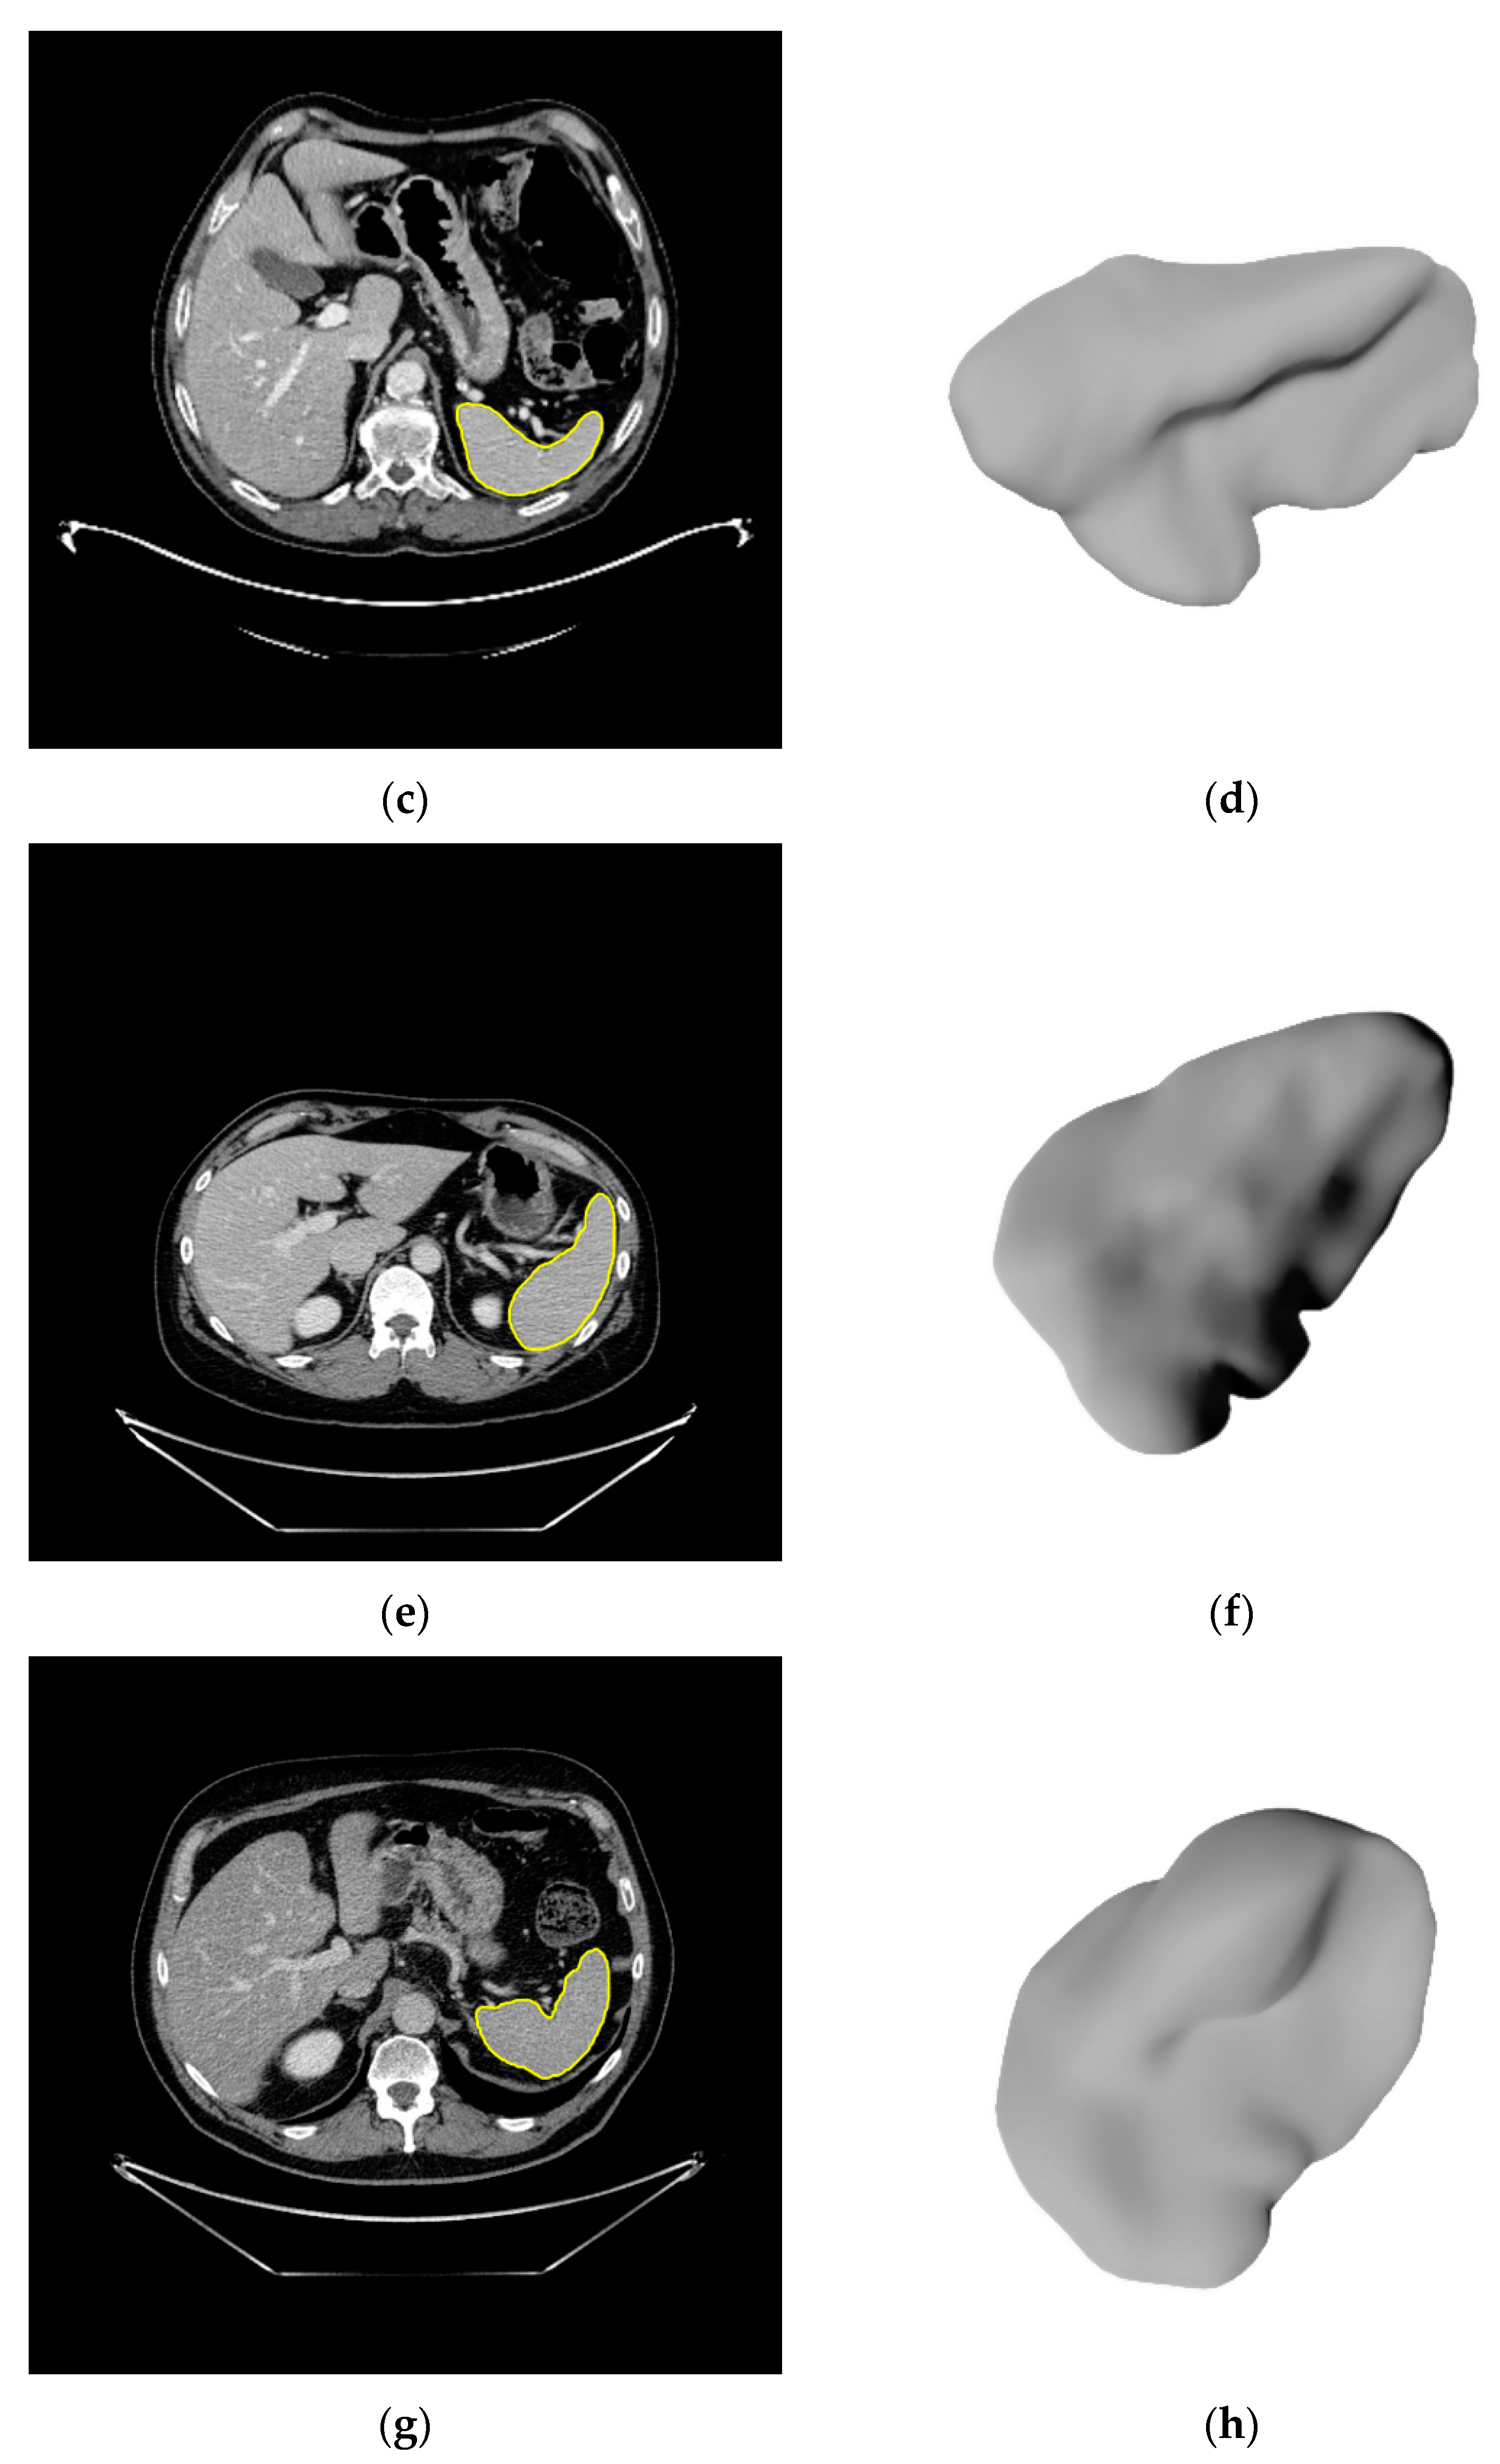

2.3. Image Segmentation

3.2. Segmentations of the Spleen